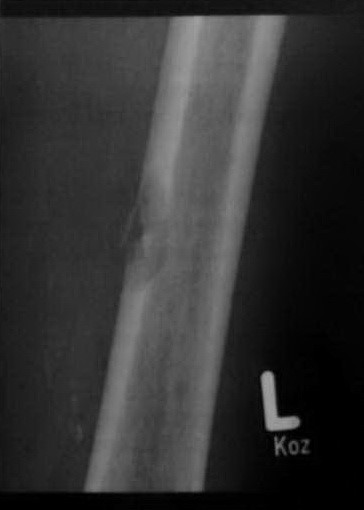

Женщина 89 лет. На рентгенограмме виден метастаз в кортикальный слой левой бедренной кости. Деструкция кортикального слоя. Первичная опухоль не установлена.